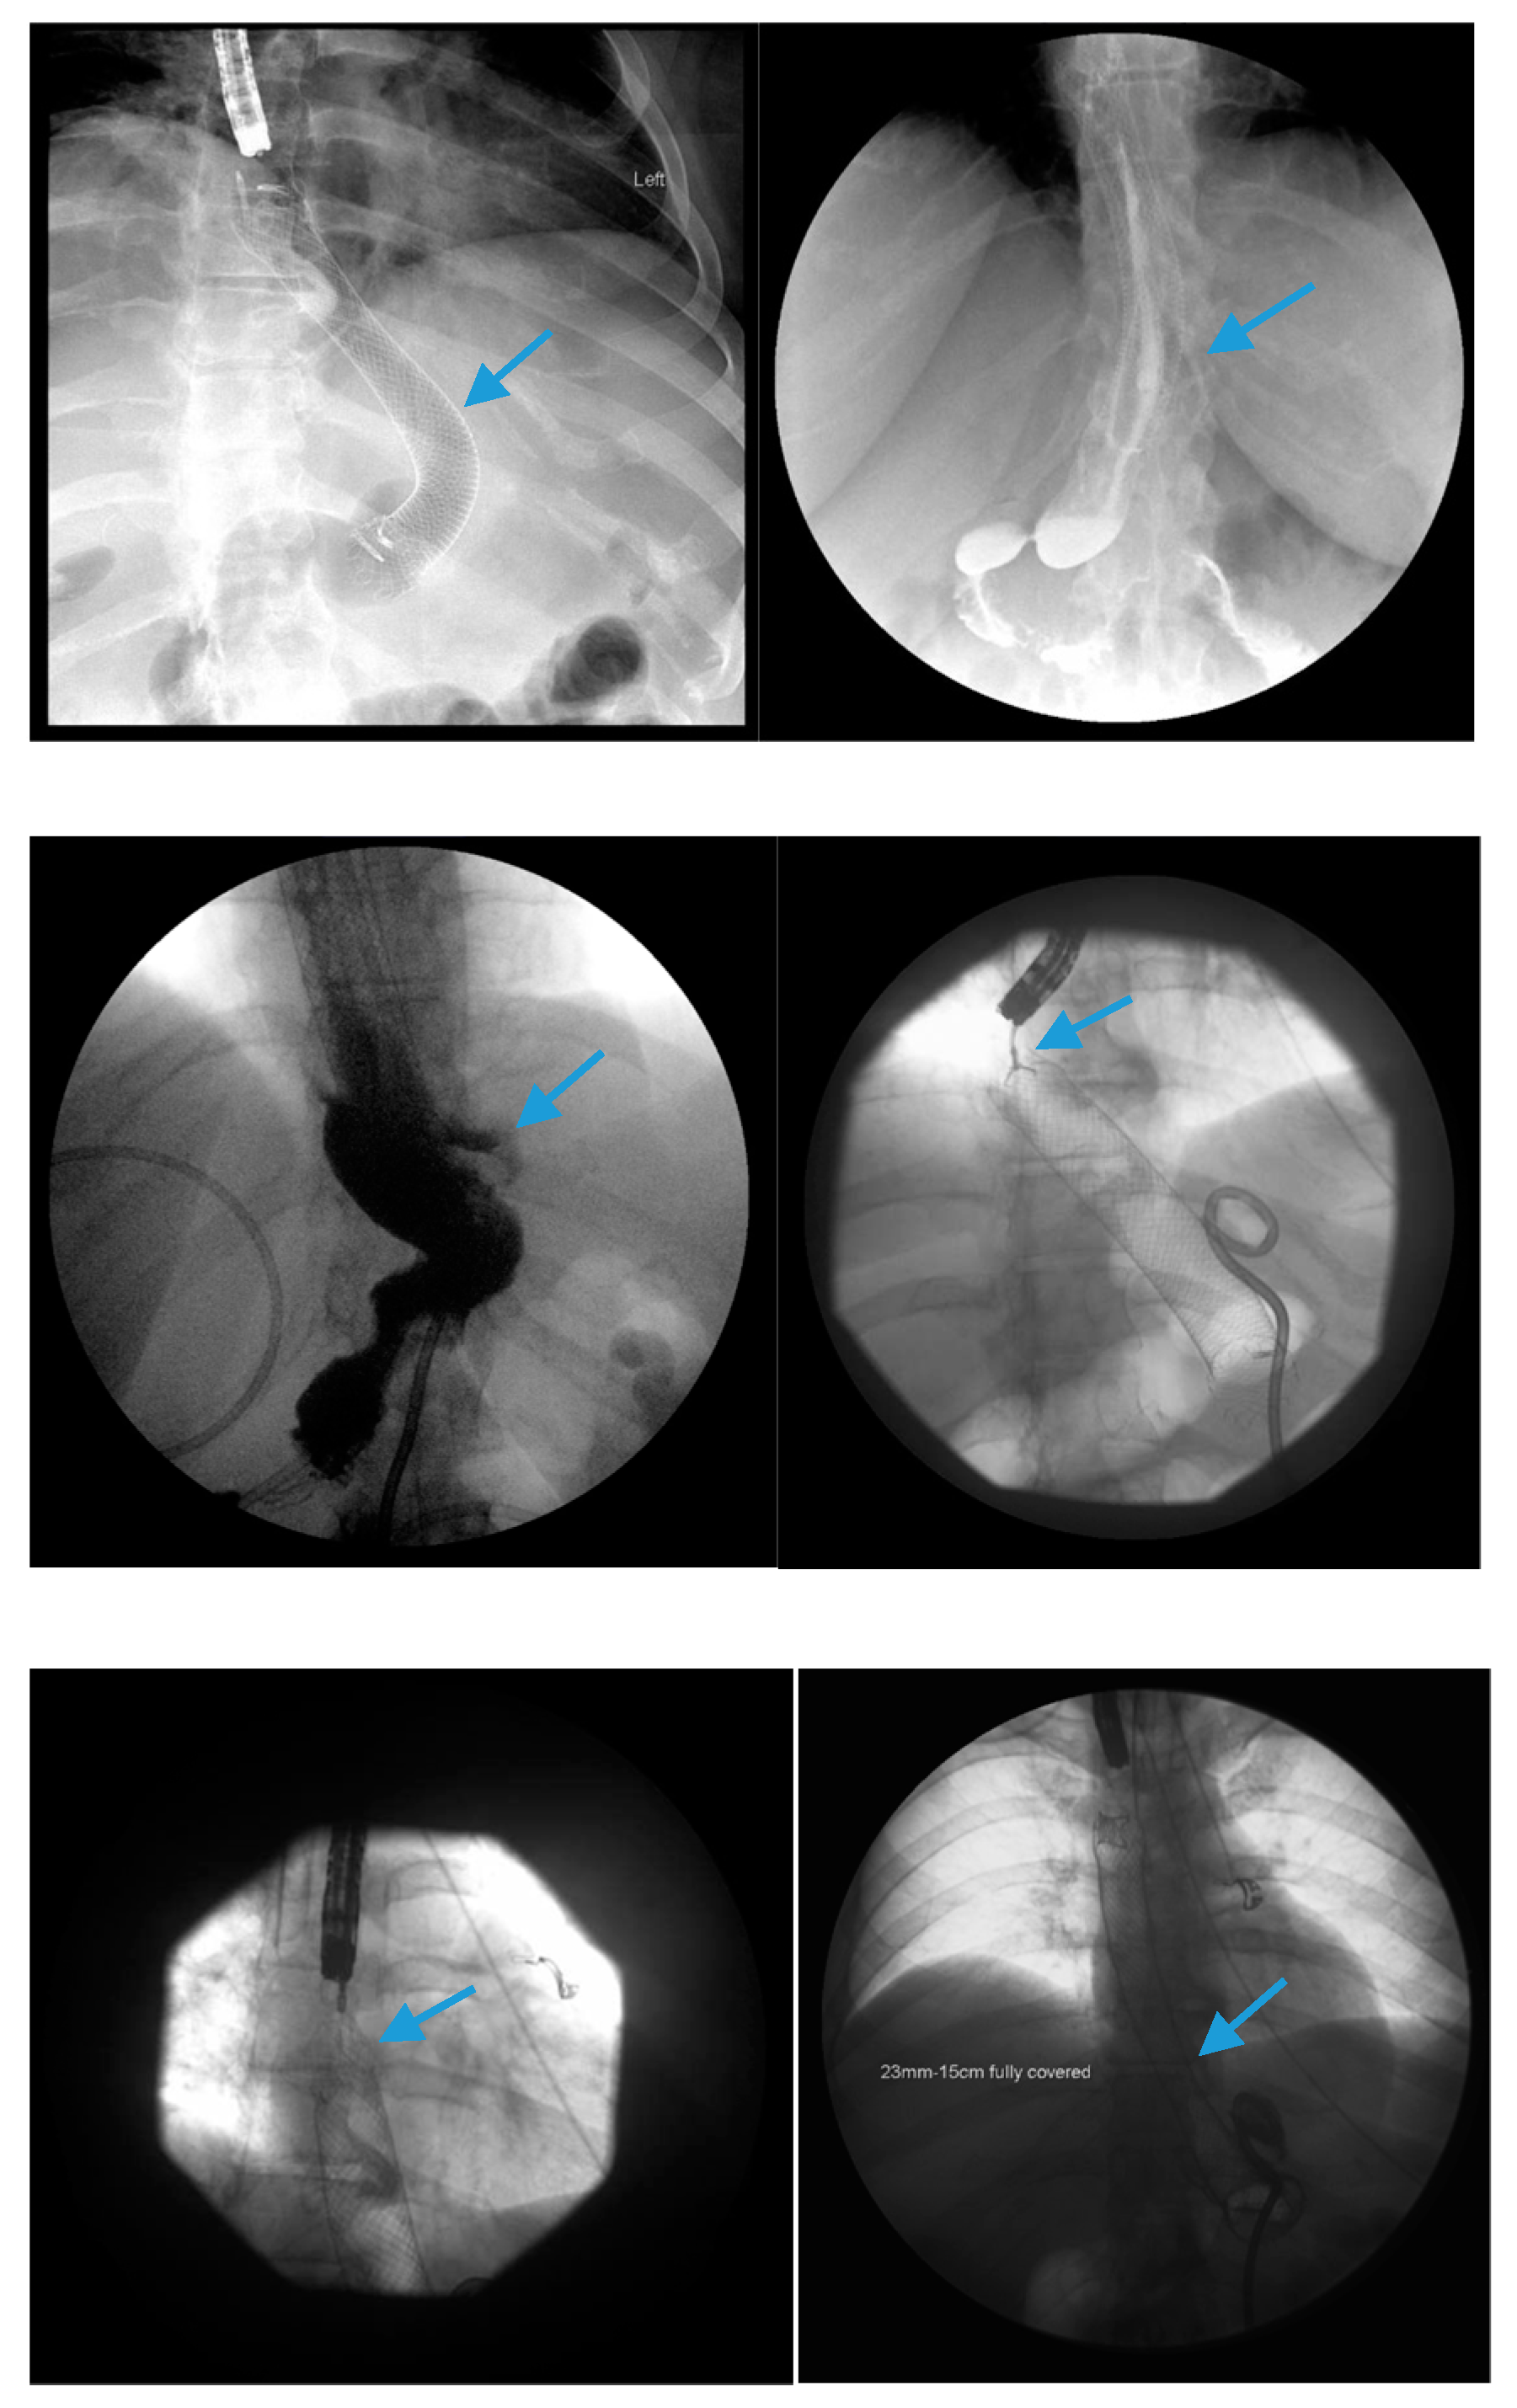

3.2. Endoscopic Stenting

3.3. Endoscopic Internal Drainage with Transgastric Double-Pigtail Stents